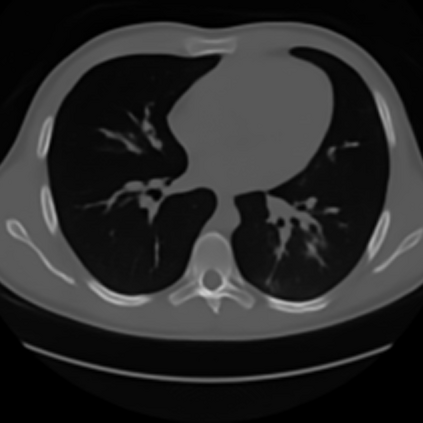

Sparse-view computed tomography (CT) -- using a small number of projections for tomographic reconstruction -- enables much lower radiation dose to patients and accelerated data acquisition. The reconstructed images, however, suffer from strong artifacts, greatly limiting their diagnostic value. Current trends for sparse-view CT turn to the raw data for better information recovery. The resultant dual-domain methods, nonetheless, suffer from secondary artifacts, especially in ultra-sparse view scenarios, and their generalization to other scanners/protocols is greatly limited. A crucial question arises: have the image post-processing methods reached the limit? Our answer is not yet. In this paper, we stick to image post-processing methods due to great flexibility and propose global representation (GloRe) distillation framework for sparse-view CT, termed GloReDi. First, we propose to learn GloRe with Fourier convolution, so each element in GloRe has an image-wide receptive field. Second, unlike methods that only use the full-view images for supervision, we propose to distill GloRe from intermediate-view reconstructed images that are readily available but not explored in previous literature. The success of GloRe distillation is attributed to two key components: representation directional distillation to align the GloRe directions, and band-pass-specific contrastive distillation to gain clinically important details. Extensive experiments demonstrate the superiority of the proposed GloReDi over the state-of-the-art methods, including dual-domain ones. The source code is available at https://github.com/longzilicart/GloReDi.